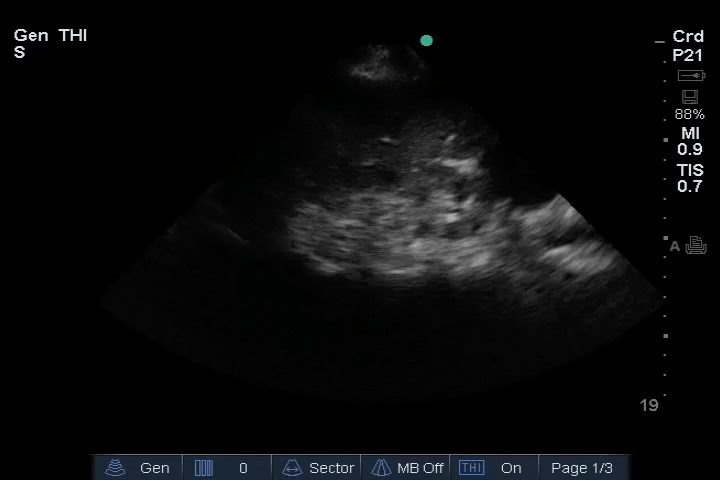

Heart: Dilated right ventricle (RV), most clearly visualized in the PSAX view. An embolus is visible in the right atrium (RA).

10_Heart_SC – Dilated RV, RA embolus

11_Heart_A4CH – Dilated RV, RA embolus